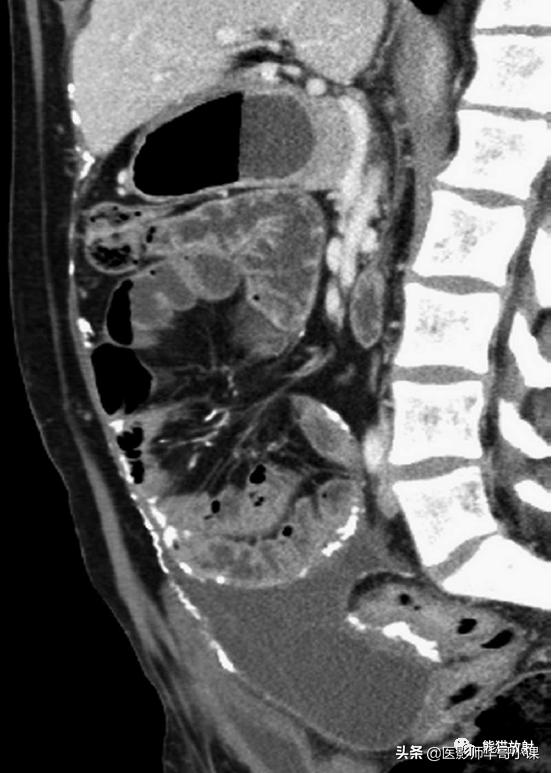

回缩性肠系膜炎CT表现 为浸润性软组织密度肿块,周围可见放射状条索影(图),这些特点可能与纤维瘤病或类癌相似。 硬化性肠系膜炎 在T1WI和T2WI图像上均呈低信号,有助于疾病的鉴别。肿块中央坏死区可见钙化(图)。该病有一定的自限性,通常预后较好。

纤维性肠系膜炎。CT表现增强CT显示大而边界模糊、广泛钙化的肠系膜软组织肿块。注意邻近的肠襻回缩及增厚。